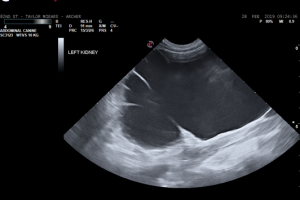

2y MI Border Collie Chief complaint: Unilateral cryptorchid; Asymptomatic. Physical examination: NSF Bloodwork (CBC/chem): NSF Abdominal ultrasound: – KIDNEYS: Left kidney (see first image below) is markedly enlarged (11cm; …